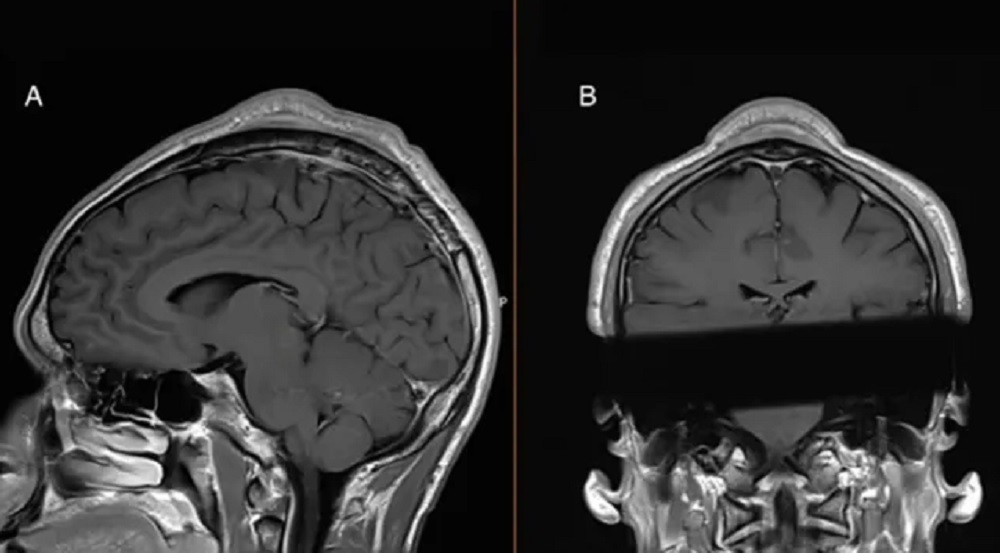

Структурное сканирование головы мужчины подтвердило это, а также показало, что кожа над шишкой и череп под ней стали толще, чем окружающие их ткани. Во время операции врачи удалили большой кусок ткани из-под черепа мужчины. Они также обрезали утолщенную часть его черепа до ее нормальной ширины.